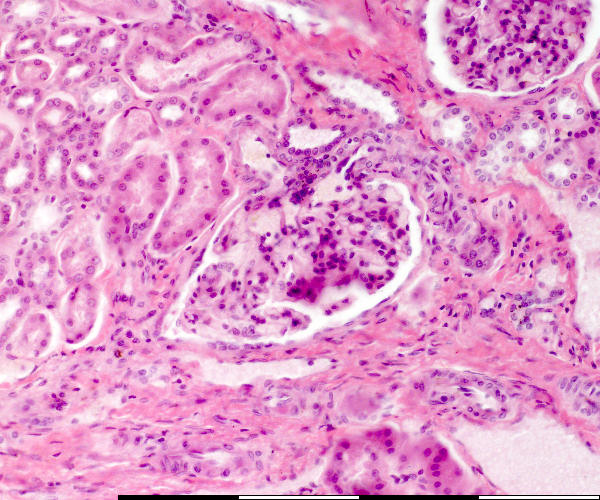

Kidney